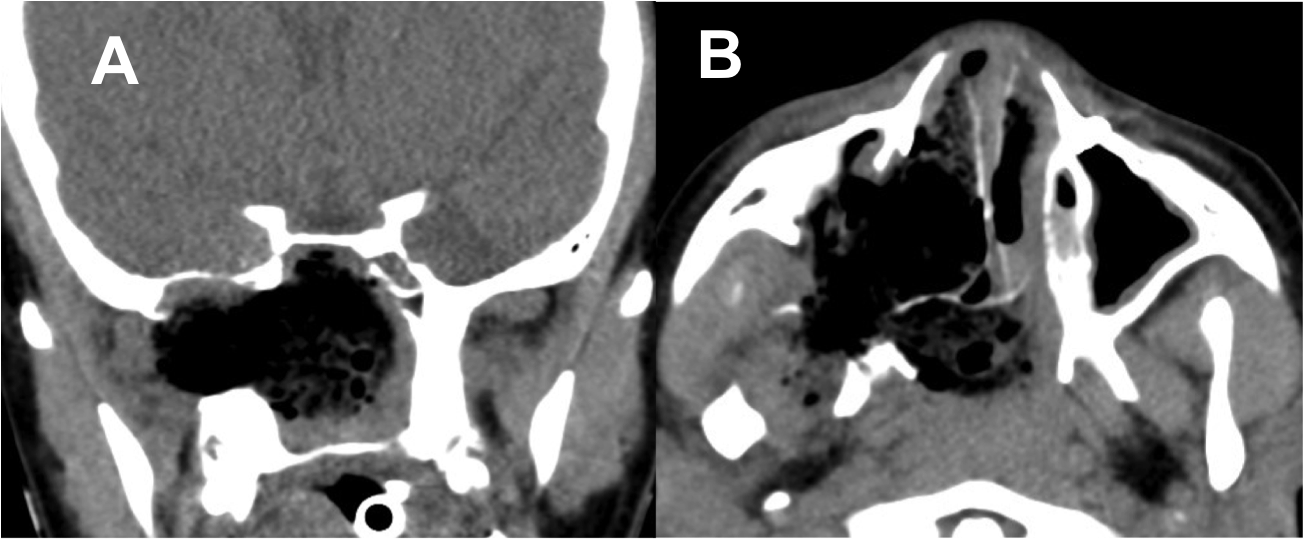

Introducción: La cirugía endoscópica endonasal se ha convertido en una herramienta fundamental para el manejo de patologías que comprometen la base de cráneo. En casos bien seleccionados, estas técnicas permiten resecciones quirúrgicas con una menor morbilidad sin comprometer los principios oncológicos de resección. Con el desarrollo de instrumental especializado, nuevas tecnologías y la experiencia de los cirujanos, la cirugía endoscópica endonasal se usa cada vez más en cirugía de base de cráneo en niños.

Diseño: Estudio observacional descriptivo de tipo serie de casos. Metodología: se describe la experiencia con pacientes pediátricos llevados a cirugía endoscópica endonasal para manejo de tumores de base de cráneo en el Instituto Nacional de Cancerología entre julio de 2014 y diciembre de 2016.

Resultados: Fueron intervenidos 8 pacientes entre los 2 y 14 años, con una edad promedio de nueve años y un seguimiento promedio de 16 meses. En el 75% se hizo una resección total del tumor. Un paciente requirió una reintervención y un paciente fue sometido a radiocirugía post-operatoria. 1 paciente falleció a pesar de múltiples intervenciones, quimioterapia y radioterapia.

Conclusión: La cirugía endoscópica endonasal para tumores de base de cráneo puede ser utilizada de forma segura en los pacientes pediátricos, es una técnica que en casos bien seleccionados pueden ofrecer excelentes resultados disminuyendo la morbilidad y complicaciones de las técnicas abiertas.